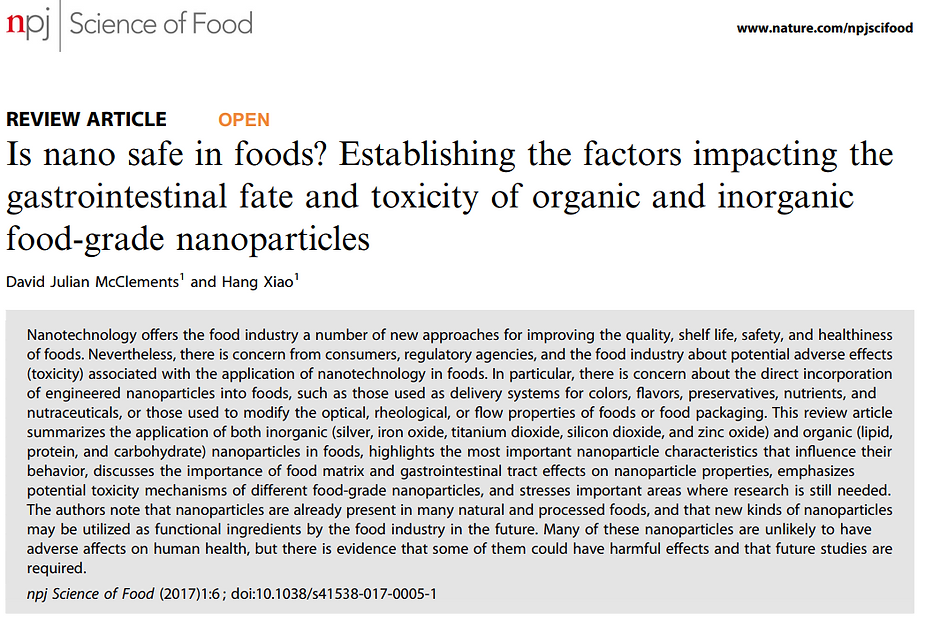

From Published Research: Science of Food, November 20, 2017, “Is nano safe in foods? Establishing the factors impacting the gastrointestinal fate and toxicity of organic and inorganic food-grade nanoparticles”, David Julian McClements & Hang Xiao

Nanotechnology offering the food industry a number of new approaches for improving the quality, shelf life, safety, and healthiness of foods. Nevertheless, there is concern from consumers, regulatory agencies, and the food industry about potential adverse effects (toxicity) associated with the application of nanotechnology in foods.

In particular, there is concern about the direct incorporation of engineered nanoparticles into foods, such as those used as delivery systems for colors, flavors, preservatives, nutrients, and nutraceuticals, or those used to modify the optical, rheological, or flow properties of foods or food packaging. This review article summarizes the application of both inorganic (silver, iron oxide, titanium dioxide, silicon dioxide, and zinc oxide) and organic (lipid, protein, and carbohydrate) nanoparticles in foods, highlights the most important nanoparticle characteristics that influence their behavior, discusses the importance of food matrix and gastrointestinal tract effects on nanoparticle properties, emphasizes potential toxicity mechanisms of different food-grade nanoparticles, and stresses important areas where research is still needed. The authors note that nanoparticles are already present in many natural and processed foods, and that new kinds of nanoparticles may be utilized as functional ingredients by the food industry in the future.

Nanotechnology can be utilized to improve food quality, shelf life, safety, cost, and nutritional benefits. In some cases, the nanomaterials used in the food industry are not intended to find their way into the final food product, e.g., those used in packaging, sensors, and antimicrobial treatments designed for sanitizing food manufacturing plants.

Engineered nanoscale materials (ENMs) may be intentionally added to foods or they may inadvertently find their way into foods (such as nanoparticles in packaging materials that leach into the food matrix). ENMs may be used to create delivery systems for nutrients, nutraceuticals, colors, flavors, and preservatives, or they may be used to modify the texture, appearance, or stability of foods. Nanoscale structures may be present in foods as the result of routinely used food processing operations, such as homogenization, grinding, and cooking.

Nanoparticles present in foods can be categorized as either organic or inorganic. Inorganic materials, such as silver, iron oxide, titanium dioxide, silicon dioxide, or zinc oxide are commonly used. These particles are either crystalline or amorphous solids at ambient temperature, which may be spherical or non-spherical, have different surface characteristics and coatings, and come in different sizes depending on the initial materials and preparation conditions used in their fabrication.

Inorganic nanoparticles:

Silver nanoparticles are used as antimicrobial agents in foods and food packaging materials.

Zinc oxide nanoparticles may be used as a source of zinc and in food packaging as antimicrobial agents to prevent contamination of foods and as ultraviolet light absorbers.

Iron oxide nanoparticles are utilized in foods as colorants or sources of bioavailable iron and come in different sizes, shapes, and crystalline forms.

Titanium dioxide nanoparticles are used as functional ingredients in certain foods to provide characteristic optical properties such as increased lightness and brightness

Silicon dioxide nanoparticles are added to certain powdered foods as anticaking agents to enhance flow properties, e.g., salts, icing sugar, spices, dried milk, and dry mixes.

Lipid nanoparticles are widely present within many commercial food products, like beverage emulsions, such as soft drinks, fortified waters, fruit juices, and dairy drinks, contain small oil droplets dispersed in water.

Protein nanoparticles are the casein micelles found in bovine milk and other dairy products, which are small clusters of casein molecules and calcium phosphate ions.

Carbohydrate nanoparticles are typically assembled from digestible or indigestible polysaccharides, such as starch, cellulose, alginate, carrageenan, pectin, and xanthan and they may be indigestible within the upper gastrointestinal tract (GIT).

Some organic substances used to fabricate food nanoparticles (such as dietary fibers and mineral oils) may not be digested in the upper GIT. Inorganic nanoparticles are also not digested in the GIT. Any nanoparticles that are not digested or absorbed in the upper GIT will reach the lower GIT where they may alter the microbiome in a negative way. The ability of inorganic nanoparticles to produce toxicity is often associated with their chemical reactivity, which depends on their composition. For example, some inorganic nanoparticles dissolve and release ions that promote undesirable chemical or biochemical reactions (e.g., silver nanoparticles).